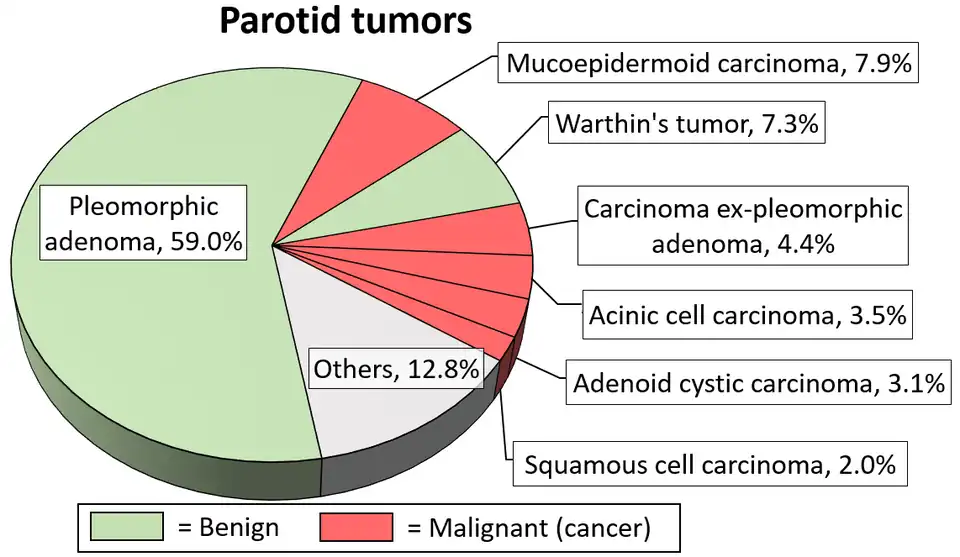

The gland most likely affected is the parotid gland. In fact, it is the only tumor virtually restricted to the parotid gland. Warthin's tumor is the second most common benign parotid tumor after pleomorphic adenoma, but its prevalence is steadily increasing.[5]

Diagrams by Mikael Häggström - ^ Psychogios G, Vlastos I, Thölken R, Zenk J (July 2020). "Warthin's tumour seems to be the most common benign neoplasm of the parotid gland in Germany". European Archives of Oto-Rhino-Laryngology. 277 (7): 2081–2084. doi:10.1007/s00405-020-05894-z. PMID 32189070. S2CID 212940703.